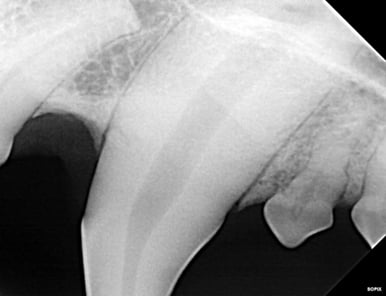

Below: Radiograph of 204 of the apex (tip of root). Beyond the wide pulp chamber, nothing significant is noted, yet studies show 43% of discolored teeth have no radiographic signs of problems, but have pulp necrosis and disease that leads to additional, potentially systemic issues.

%20-%20March%202024/Radiograph%20before%20RCT%20-%20apex.jpg?width=386&height=297&name=Radiograph%20before%20RCT%20-%20apex.jpg)

Below: Before RCT - Radiograph of 204 to aid in planning the access point

%20-%20March%202024/radiograph%20before%20RCT%20-%20access%20point.jpg?width=386&height=297&name=radiograph%20before%20RCT%20-%20access%20point.jpg)